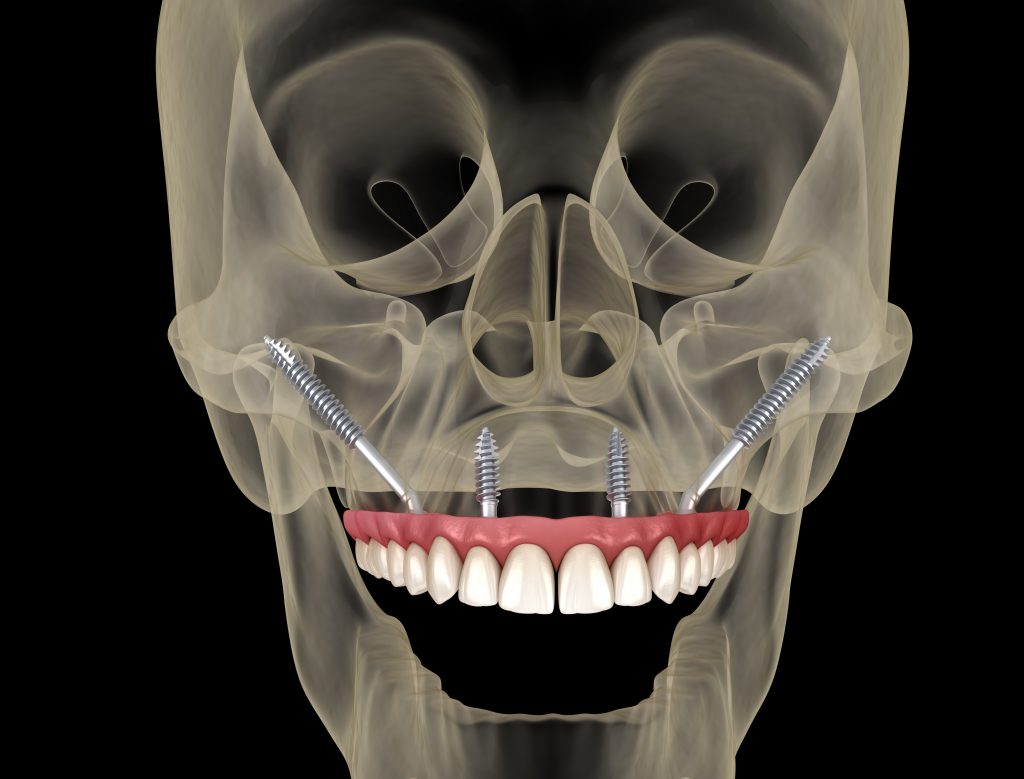

Los implantes cigomáticos son un tipo de implante dental especialmente diseñado para pacientes que no tienen suficiente hueso en el maxilar superior. A diferencia de un implante convencional, que se fija en el hueso del maxilar, el implante cigomático es más largo y se ancla en el hueso cigomático (el pómulo), una zona muy densa y estable que siempre mantiene suficiente estructura ósea, incluso cuando el maxilar está muy reabsorbido.

El número de implantes cigomáticos necesarios suele variar entre 1 y 4 por arcada y depende principalmente de la calidad del hueso maxilar y la calidad del hueso cigomático (pómulo). Cuando el hueso del maxilar no es suficiente, utilizamos el hueso cigomático (el pómulo) como punto de anclaje.

Sin embargo, cuando no existe buen hueso maxilar en ninguna zona, o incluso cuando el punto de apoyo en el pómulo no ofrece la estabilidad ideal, pueden necesitarse hasta 4 implantes cigomáticos para conseguir una fijación segura y permitir una rehabilitación fija inmediata.

Un implante cigomático mide entre 35 mm y 55 mm, mucho más que un implante dental convencional, que suele medir entre 8 y 18 mm. Su longitud permite alcanzar el hueso del pómulo para ofrecer la estabilidad necesaria en casos de atrofia ósea severa.